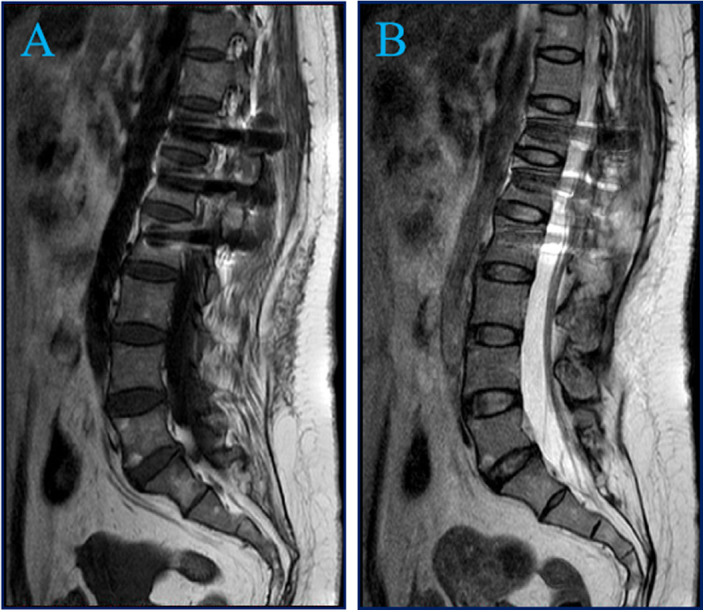

A 51-year-old female with a 10-year history of progressive low back pain presented with a 9 × 15 mm circular tumor adjacent to L1 on preoperative magnetic resonance imaging. The lesion was successfully removed by T12-L2 laminectomy and nail-rod fixation. Histopathological examination diagnosedmature intramedullary cystic teratoma. At 6-month follow-up, right lower limb numbness and pain were reduced.